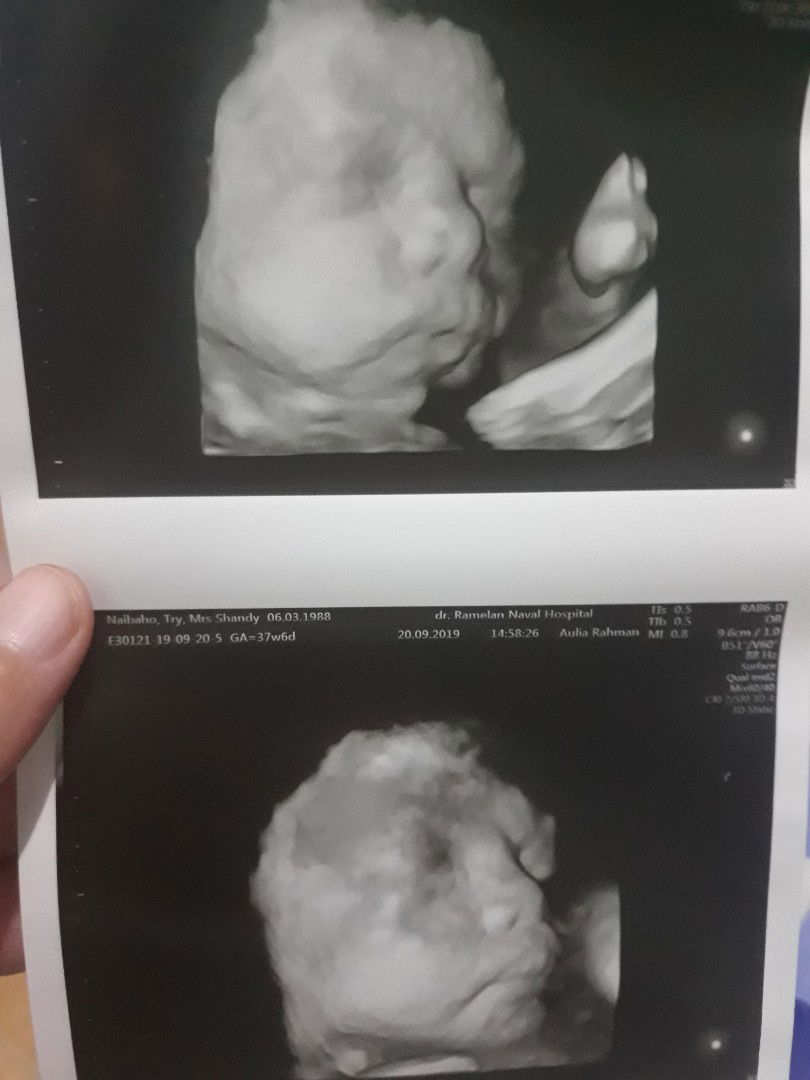

Bund, kmren saya sempat share kan tntg kepala bayi saya yg melintang, kepalanya di swbelah kanan. Pdhal slama ini kepalanya sdh dibawah, ttp entah knp pas usg rabu 18 september kemaren kepalanya tiba2 dikanan. Nah, suami saya kasihan lihat saya nangis trus krn kepikiran mslah itu. Akhirnya suami saya jumat kmren memutuskan untuk ganti dokter dan usg ulang. Suami saya ngajak saya Usg di Rumah sakit tentara surabaya dan usg 4d. Sesampainya disana dokter sempat meraba dulu letaknya dimana sebelum di usg, trnyta letak kepalanya malah muter lagi bund jd kesebelah kiri. Priksa punya priksa akhirnya di USG lah. Tp dokter sdh mengatakan bhwa USG kali ini walaupon 4D kemungkinan wajahnya tdk akan kelihatan lagi krn sdh besar dan kemungkinan wajah baby nya sdh menghadap punggung ibu, dan memang benar. Ttp kami tdk terlalu mengharapkan bagaimana wajahnya, kami hny mengharapkan posisi letak kepala bayi saya. Singkat crt bund, akhirnya hasil yg kami tunggu2 pon dpt, Alhamdulillah letak kepala bayi saya di bawah. Saya tdk tau apakah dia muter lagi, atau hasil usg dokter sebelumnya yg salah. Ttp yg penting kami bersyukur kepalanya dibawah, krn saya sempat stres mikirinya. Dan memang bener wajah baby saya sdh menghadap ke punggung saya jd wajahnya tdk dpt. Ttp tau ga bund, ga lama kemudian, baby saya gerak2 dan trnyta dia menunjukkan wajah nya, sehingga dokter kaget dan cpt2 jepret wajahnya. Seneng bgt bund ketika lihat wajahnya. Sang dokter pon ketawa dan mengatakan anak ibu pinter, dia tdk mau buat kuatir org tuanya. Dia memberitahukan bhwa dia baik2 saja dan menunjukkan wajahnya. Saya dan suami senang bgt ketika melihat wajahnya. Dan saya bertrimakasih kpd Tuhan anak saya sehat, tdk ada apa2. Bagi saya ini adlah muzijat.skrg saya hny tinggal menunggu kelahirannya. Berikut adlah wajah baby saya dikandungan. Kata temen2 sih mirip ayahnya